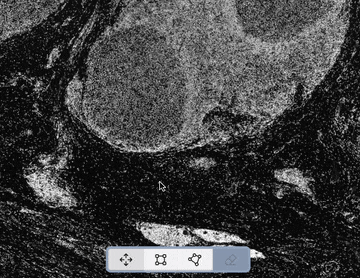

In the summer prototype - which you may remember from the demo video - our image viewer looked like this:

By the end of November, it looks like this:

Sundog users are going to spend a lot of time in the Viewer, and we're really pleased with how it's turning out. This window-filling design, with interaction that feels much closer to a desktop app, is definitely a huge leap in the right direction. It’s technically challenging work, but I can’t also deny that it’s just fun to be inside, to manipulate, and that makes the effort woth it.